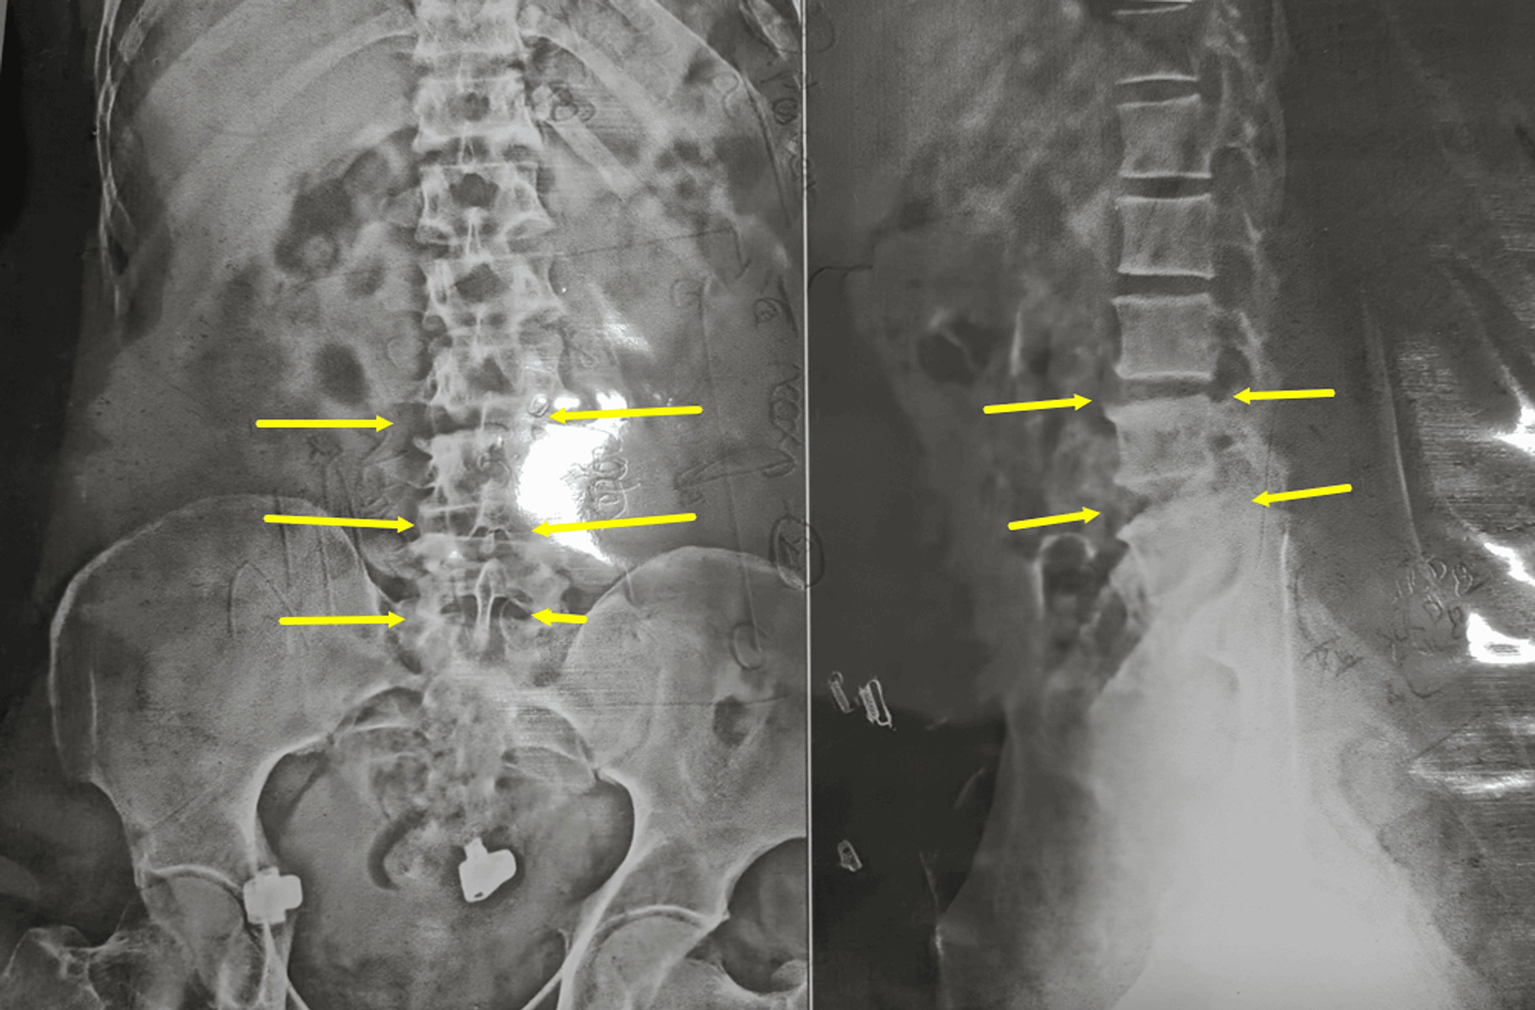

An Ayurvedic assessment identified a Vata dosha imbalance. Vata is the principle governing movement and nervous system function. The patient's pain radiated from the gluteal region to the upper and lower back, knee, and sole of the left foot, consistent with the Ayurvedic diagnosis of Ghridhrasi. Furthermore, the patient's gait exhibited a vulture-like limp, further supporting this diagnosis with a Vata-dominant subtype (Fig. 1, Fig. 2, Fig. 3).

Fig. 1. X-ray of the Lumbar spine (AP view) showing degenerative changes from L3 to S1